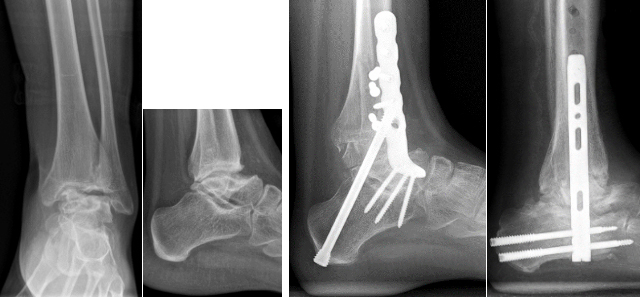

Bei voroperierten Patienten oder Patienten mit größeren Knochendefekten wie bei einer Hämophilie A (Bluter-Krankheit) sind komplexere Techniken mittels Verplattungen oder retrogradem Einbringen eines Marknagels unter Mitnahme des unteren Sprunggelenkes notwendig. Teilweise muß der knöcherne Defekt dann mittels Knocheninterponat überbrückt werden.

Versteifung des oberen und unteren Sprunggelenkes mit Knocheninterponat bei hämophilem Patienten (linke 3 Bilder) - Revision mittels retrogradem Nagel